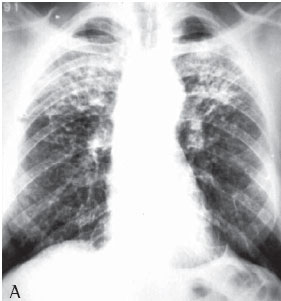

RESULTS

All 75 patients with accelerated silicosis were male. The mean age was 43 years (range, 28-76 years). The mean duration of exposure was 14.2 years (range, 7 months-38 years). Of the 75 patients, 62 (82.6%) were sandblasters, 11 (14.6%) were blacksmiths, 1 (1.4%) was a welder, and 1 (1.4%) was a metal polisher. In reference to concomitant tuberculosis, 39 patients reported a history of pulmonary tuberculosis (52%). Of those, 37 developed the disease during their exposure to silica.The diagnosis was confirmed in 31 cases: 24 through direct sputum smear microscopy; 3 through direct mycobacteria culture of the sputum; 1 through mycobacteria culture of the bronchoalveolar lavage fluid; and 3 through histopathology. In 8 patients, there was clinical and radiological suspicion of tuberculosis based on a response to specific treatment. The radiological classification of the large opacities seen on the chest X-rays was as follows: Type A in 23 patients (30.7%); Type B in 25 (33.3%); and Type C in 27 (36%) (Figures 1A and 1B). Of the cases analyzed, 74 presented bilateral conglomerate masses, whereas only 1 presented unilateral lesion (Figures 2A and 2B).

Of the 75 PMF patients, 44 underwent chest HRCT. The HRCT scans revealed that 88.6% of the masses were located in the upper thirds of the lungs and were posterior. Cavitations were observed in 18.18% of the masses, air bronchogram in 70.4% and internal calcification in 63.6%. Emphysematous lesions surrounding the masses were observed in 72.7%, and lymph node calcification was seen in 81.8% (Figures 3A and 3B).

On a simple chest X-ray, accelerated silicosis is characterized by large opacities (over 1 cm in diameter), with nonsegmentally distributed, homogenous areas of consolidation, principally affecting the upper fields.

The lesions tend to form on the periphery, migrating toward the hilum, creating a zone of emphysematous lung tissue between the consolidation and the pleural surface. The borders of the large opacities are irregular and poorly defined. As the disease progresses, the masses tend to shrink. Emphysematous lesions and bullae then appear surrounding the masses and at the lung bases. The lungs gradually lose volume. The large masses seen in accelerated silicosis are capable of causing cavitation due to the resultant ischemia and necrosis. Nevertheless, cavitation is a relatively uncommon finding in silicosis. When it does occur, one should first consider tuberculosis. The pleural thickening frequently observed in tuberculosis is also commonplace in PMF, although pleural effusion is extremely rare.(17)

The greater the profusion of nodules on the chest X-ray (categories 2 and 3), the greater are the odds of evolving to PMFThe chest X-ray generally shows large lung opacities against a background of diffuse pulmonary nodule formation. However, PMF has been reported in the absence of pulmonary nodule formation, since the silicosis nodules present reduced visibility due to their incorporation within the fibrous mass.(18)

The chest X-rays of more than half of the accelerated silicosis patients showed large type B or C opacities, denoting the seriousness of the disease in these patients.

In the present study, chest HRCTs revealed that the large opacities were predominantly (in 88.6% of the cases) located in the upper and posterior thirds of the lung.Air bronchograms and calcifications within the masses were found in over half of the patients. Calcified hilar and mediastinal lymph nodes were observed in 81% of the cases, 25% being of the eggshell type. Only 8 cases displayed cavitation within the masses, 6 presenting concomitant tuberculosis.